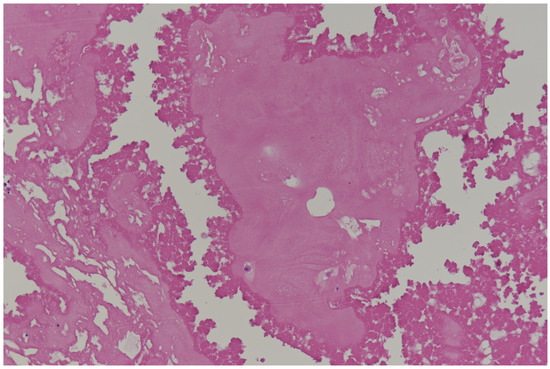

2. Primary Benign Cardiac Tumors